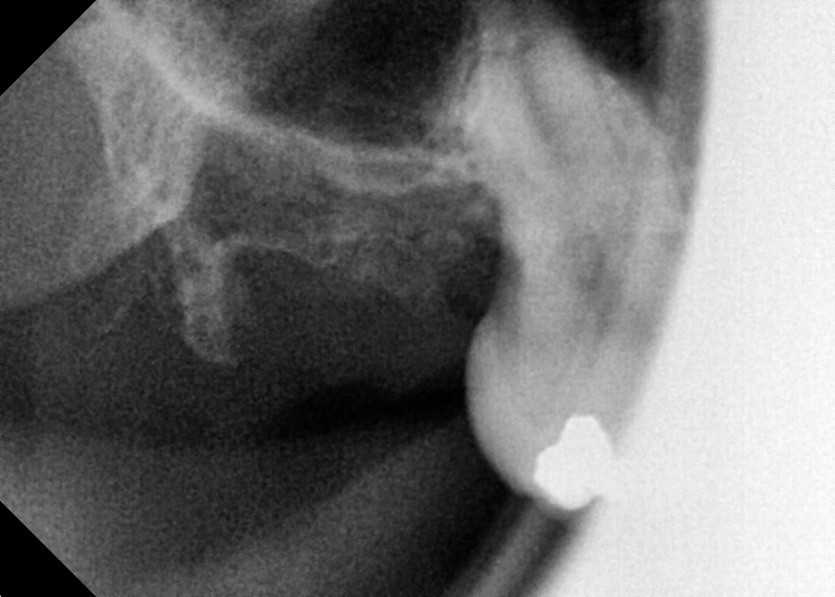

#18 사랑니 발치

구강 외과 전문의가 당일 발치했습니다.